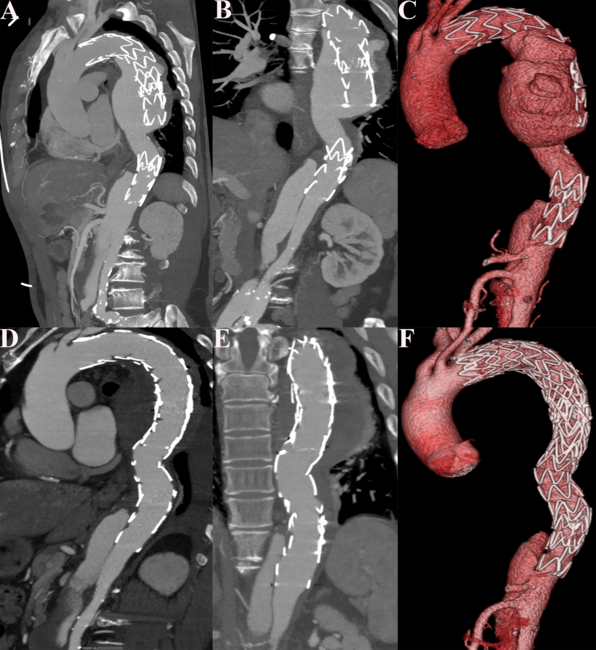

A 67-year-old man was referred to our hospital because of stent leakage after thoracic endovascular aortic repair (TEVAR) for type B aortic dissections (TBAD) 6 years ago. Computed tomographic angiography (CTA) revealed distal stent graft-induced new entry (dSINE) with endoleak (Figure A-C). Subsequently, the aortic angiography confirmed the dSINE and endoleak (Video 1).

The patient underwent re-TEVAR with 2 Valiant thoracic stent grafts (Medtronic) measuring 32 x 28 x 150 mm and 36 x 36 x 200 mm. Postoperative CTA and aortic angiography confirmed a successful repair of the dSINE and endoleak (Figure D-F, Video 2). The postoperative course was uneventful, and he was discharged after 7 days. At the 12-month postoperative follow-up, no migration, deformation, or new endovascular leakage were observed.